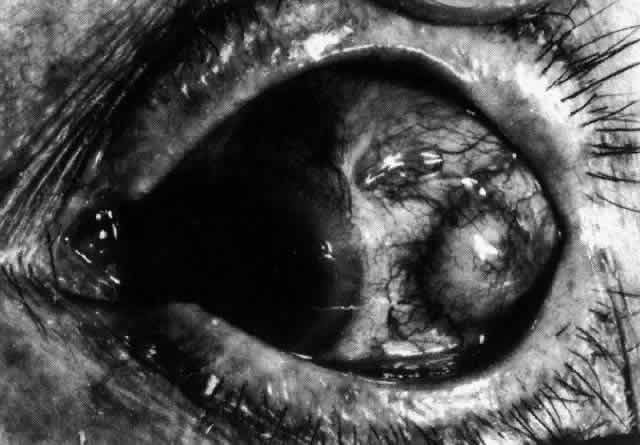

episcleritis and nodular episcleritis. ETIOLOGY Thirty percent of patients with episcleritis had some associated general conditions,6–8 but the rest defied all attempts to discover an etiology. Although some patients had a strong family history of atopy, results of patch and prick testing were uniformly negative. Of those in whom an etiology was found, only 5% showed any association with collagen disease, 7% had an association with herpes zoster, and 3% each had an association with gout or syphilis; the rest had associated conditions such as erythema nodosum, Schönlein-Henoch purpura, erythema multiforme, contact with industrial solvents, or penicillin sensitivity, indicating an immune basis for the condition. PATHOLOGY Microscopic and electron microscopic studies of biopsy specimens from patients with simple and nodular episcleritis have been totally noncontributory in the attempt to discover the etiology of this condition. The inflamed area is packed with lymphocytes and a few other inflammatory cells, but there are no mast cells, plasma cells, or eosinophils. CLINICAL MANIFESTATIONS The onset is usually acute; the eye may become red and painful in as short a time as half an hour. The patient's main complaint is redness of the eye, which is often sectorial and may be accompanied by a feeling of hotness, pricking, and mild discomfort. There is no discharge, although the eye waters occasionally. Pain may be absent, but the discomfort may be so severe that patients cannot pursue their normal occupation. The pain is localized to the eye, rarely radiating to the forehead and never producing the severe boring pain that is so commonly described in scleritis. In a severe attack the lids may become swollen, but this is a rare occurrence. If photophobia is present, an accompanying corneal condition should be suspected. Simple and nodular episcleritis differ in their clinical courses, but in both the edema and infiltration are entirely within the episcleral tissues. The sclera is not involved. The maximum congestion is in the superficial episcleral network, with some slight congestion of the conjunctival vessels and deep episcleral vessels (Fig. 10). The intraocular structures are not involved in either variety, nor is the visual acuity affected. Anterior segment fluorescein angiography reveals a normal vascular pattern but a very rapid flow rate, with the whole transit of the dye being completed within 2 or 3 seconds (Figs. 11 and 12).

The redness of simple episcleritis may be intense, varying from a fiery-red or a brick-red discoloration to a mild red flush, but it does not have the bluish tinge that is seen in scleritis. The distribution is usually sectorial but can involve the whole anterior segment of the globe. The episcleral vessels are engorged but retain their normal radial position and architecture (Figs. 13 and 14; Color Plate 1A). In simple episcleritis, there is a diffuse edema of the episcleral tissues. These tissues are sometimes infiltrated with gray deposits that appear yellow in red-free light. Surprisingly, the eye is rarely tender to the touch.